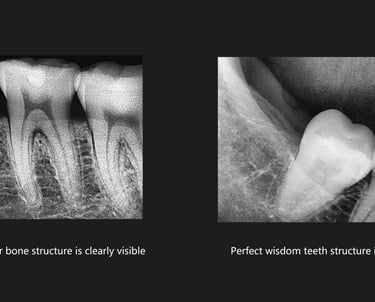

High-Resolution Imaging: The system provides high-quality images, allowing for accurate diagnosis of dental conditions, including cavities, root issues, and other oral health concerns.

Periodontics: Helps in diagnosing periodontal disease, bone loss, and other related conditions by providing detailed imaging of the jawbone and surrounding tissues.